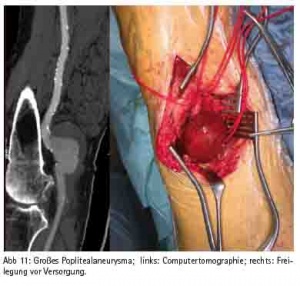

Brustkorbschmerzen gehört zu den häufigsten Einweisungsdiagnosen einer Notaufnahme, auch im Bundeswehrzentralkrankenhaus Koblenz. Seit 2010, rezertifiziert 2013, verfügt das Bundeswehrzentralkrankenhaus über eine Chest Pain Unit. Hier werden Patienten mit Brustkorbschmerzen optimal diagnostiziert und therapiert. Moderne Bildgebung stellt eine der wichtigen Säulen in der Diagnostik dar. Gerade in der Notaufnahme beginnt die suffiziente Untersuchung des Patienten mit einem im Bedarfsfall angezeigten triple-rule-out CT (Ausschluss signifikante KHK, Aortendissektion und Lungenarterienembolie in einer CT-Untersuchung) oder Koronar-CT (Abb. 1). Akute ST-Hebungsinfarkte werden gemäss den aktuellen Leitlinien (2014 ESC/EACTS Guidelines on myocardial revascularization) sofort ins Herzkatheterlabor verbracht und hier einer Koronarintervention mit Wiederöffnung des verschlossenen Koronargefäßes unterzogen. Diese therapeutischen Optionen müssen 24/7 angeboten werden, da viele kardiovaskuläre Notfälle sich außerhalb der regulären Dienstzeit ereignen, z. B. in den frühen Morgenstunden mit Aktivierung des sympathischen Nervensystems. Die Wiederherstellung der Reperfusion beim STEMI innerhalb der ersten 2 – 3 Stunden nach Symptombeginn muss unbedingt angestrebt werden. Jede Zeitverzögerung führt zu einer Prognoseverschlechterung. Im Idealfall wird das Herzkatheterteam bereits über den Notarztwagens bzw. die Rettungsleitstelle informiert, so dass beim Eintreffen eines NAW’s der Patient direkt ins Herzkatheterlabor verbracht werden kann und eine Wiedereröffnung der Koronargefäße erfolgt. Wenn ein Patient mit einem akuten ST-Hebungsinfarkt sich ohne Rettungsmittel direkt in der Notaufnahme vorstellt, ist eine door-to-ballon (Zeit zwischen betreten der Notaufnahme und Wiedereröffnung des Herzkranzgefässes im Herzkatheterlabor) unter einer Stunde anzustreben. Nur in Ausnahmefällen, wie z. B. im Auslandseinsatz sollte die Thrombolysetherapie noch als alternative Therapie wegen schlechterer Wiedereröffnungsraten des Koronargefäßes mit höheren Komplikationsraten durchgeführt werden. Gemäß den gültigen Leitlinien ist auch bei erfolgreicher Thrombolysetherapie eine zeitnahe Koronarangiographie anzustreben, da aufgrund des rupturierten Plaques nur der adhärente Thrombus durch die Thrombolysetherapie beseitigt wird und bei unveränderter Plaquemorphologie ein hohes Reinfarktrisiko besteht. Auch bei Patienten mit einem NSTEMI (Nicht-ST-Hebungsinfarkt), der sich prognostisch langfristig kaum von dem Risiko eines ST-Hebungsinfarktes unterscheidet, ist eine zeitnahe Koronarangiographie anzustreben, insbesondere wenn die Patienten hämodynamisch instabil sind, einen relevanten Troponinanstieg (bevorzugt werden sollte das hochsensitive Troponin), dynamische ST- oder T-Wellenveränderungen im Ruhe-EKG aufweisen oder der Grace score (http://ww.gracescore.org) über 140 liegt. Insbesondere beim STEMI (ST-Streckenhebungsinfarkt) kann eine additive Thrombusaspiration über einen speziellen Herzkatheter bei großer Thrombuslast im verschlossenen Koronargefäss hilfreich für eine erfolgreiche Reperfusionsstrategie sein (Abb. 2).